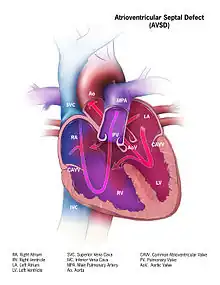

Atrioventricular septal defect (AVSD) or atrioventricular canal defect (AVCD), also known as "common atrioventricular canal" or "endocardial cushion defect" (ECD), is characterized by a deficiency of the atrioventricular septum of the heart that creates connections between all four of its chambers. It is a very specific combination of 3 defects:

1) Atrial Septal Defect (ASD), a hole in the wall between the right and left atria;

2) Ventricular Septal Defect (VSD), a hole in the wall between the right and left ventricles; and

3) Abnormalities of the mitral and/or tricuspid valves.[1][2]

- In the complete AVSD (CAVSD), there is a large ventricular component beneath either or both the superior or inferior bridging leaflets of the AV valve. The defect involves the whole area of the junction of the upper and lower chambers of the heart, i.e. where the atria join the ventricles. There is a large hole between the lower portion of the atria and the upper or 'inlet' portion of the ventricles and this is associated with a significant abnormality of the valves separating the atria from the ventricles. The valves in effect become a common atrio-ventricular valve, and the severity of the defect depends largely on the supporting attachments of the valve to the ventricles and whether the valve allows dominant flow from the right atrium to right ventricle and from left atrium to left ventricle ("unbalanced" flow). The overall problems are similar to those of VSD but are more complicated. There is an increased flow of blood to the lungs through both the ventricular and atrial components of the defect. In addition, the abnormal atrio-ventricular valve invariably leaks, so that when the ventricles contract, blood flows not only forwards to the body and the lungs, but also backwards into the atria. The back-pressure effect on the atria causes congestion of blood in the left atrium in particular, and this in turn causes congestion in the veins draining the lungs. The effect on the baby is to worsen the heart failure that is associated with an isolated VSD and to hasten the onset of pulmonary hypertension. It should be mentioned that CAVSD is found in approximately one-third of babies who have Down syndrome, but it also occurs as an isolated abnormality.